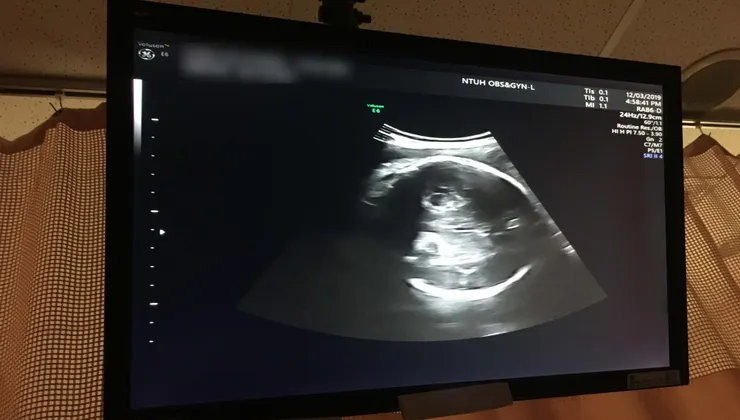

當時的小凱莉只有25+6週,體重852克。

每4天換針一次,左右手佈滿針孔;每7天要從子宮頸取細菌做培養﹙這取樣超痛﹚,確認沒有會影響寶寶的細菌;最期待的就是每個禮拜一的寶寶超音波,護理師會推床到檢查室,看到凱莉健康的待在肚子裡,雖然長大速度略慢,但至少她很努力,我也就更有動力的躺平安胎。

長時間的平躺,讓我的屁股長了褥瘡、背部濕疹、皮膚乾燥癢,加上屁股的凸出骨頭破皮,分分秒秒都痛得我難耐,努力撐到了34週,凱莉超音波預測已破2000克,和老公討論後決定先停止高貴藥的注射,保留健保藥劑就好。高貴藥的停止,讓我開始感覺到心跳加速和頻繁的宮縮,羊水也一直流出,但過了一天之後,我的宮縮被健保藥控制住了;又過了3天,34+3週的早上10點,我們決定把健保藥也移除,口服安胎藥也停止服用;當天下午4點,我開始落紅,還來不及等乙型鏈球菌的報告出爐,凱莉已迫不及待的想跟我們見面。努力了30個小時,2019/12/07 34+4週早上10點多,凱莉已平安健康的來到這個世界上。